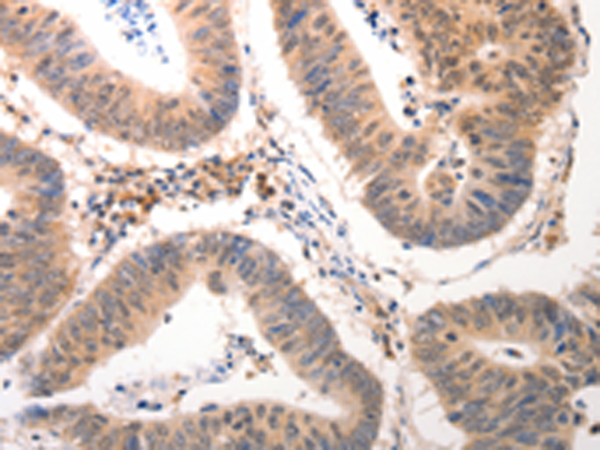

分类: 科研抗体货号: P10723别名: KGF; HBGF-7应用: IHC反应种属: Human, Mouse, Rat